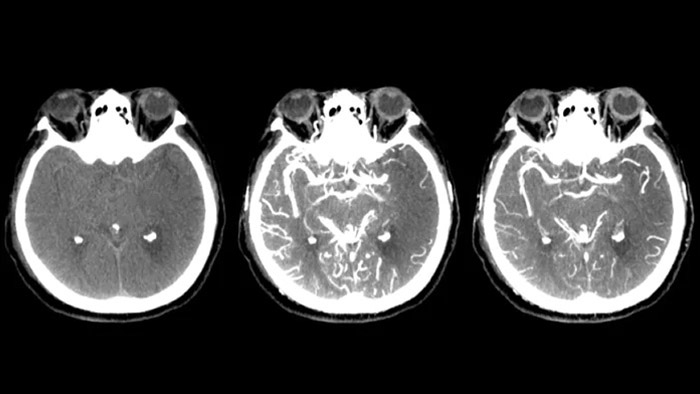

Three smart CTs

CT-like visualization of soft tissue, bone and vascular structures.

SmartCT Soft Tissue is an X-ray acquisition technique that generates a CT-like visualization of soft tissue in relation to other structures during procedures – all controlled via the touch screen at the table. You can use the CT-like imagesto assess soft tissue, bone structure and stent deployment before, during and after interventional procedures.

Peri-procedure check of bleedings

SmartCT soft tissue

Use SmartCT Soft Tissue images in the neurovascular suite to help identify peri-procedural bleedings.